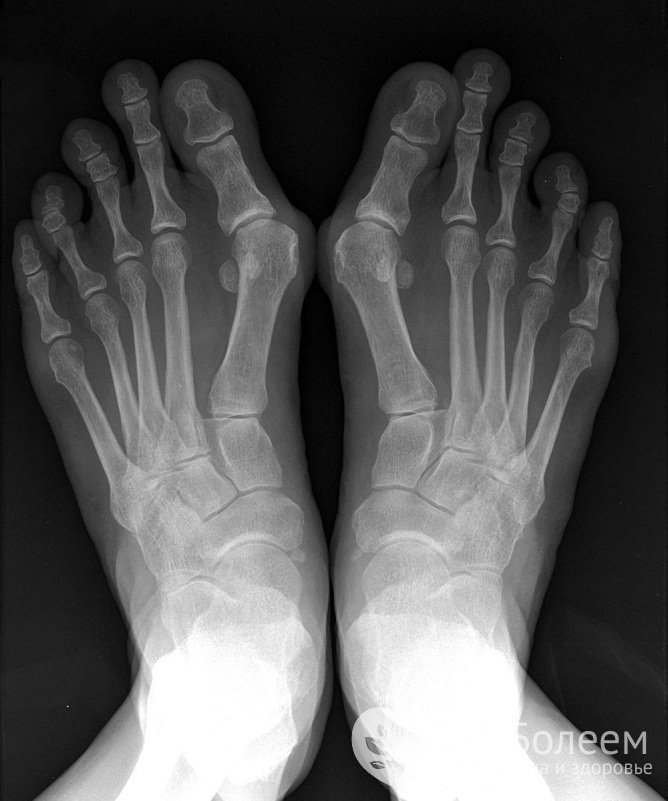

Специфические симптомы присущи лишь некоторым формам заболевания. Для реактивного артрита характерно несимметричное воспаление суставов конечностей на фоне лихорадки, головной боли и конъюнктивита. В некоторых случаях добавляются признаки инфекции мочеполовых путей. Вальгусные деформации больших пальцев рук и ног дают основание заподозрить подагрический артрит, а в случае псориатического артрита сильно деформируются и утолщаются суставы кисти.

Ревматоидная стопаСуществуют две формы артрита, которые диагностируются исключительно в детском возрасте – ювенильный идиопатический артрит и ювенильный ревматоидный артрит, или болезнь Стилла. Для обоих заболеваний характерно персистирующее течение и слабый ответ на терапию, при болезни Стилла кроме суставов часто поражаются внутренние органы.

Прохождение МРТ гарантирует максимальную точность диагностики суставных патологий за счет качественной визуализации твердых и мягких тканей. Рентгенография и КТ сустава в прямой, боковой и косой проекции позволяют выявить изменения со стороны костного аппарата. Для оценки состояния хряща, сухожилий, связок, мышц и нервов дополнительно назначают УЗИ крупных суставов. При повреждении коленного сустава может потребоваться артроскопия с отбором синовиальной жидкости и биоптата. В целях отслеживания динамики процесса в отсутствие обострений может быть целесообразна контрастная артрография.

Для диагностики артрита делают рентген, МРТ или КТЛабораторная диагностика артрита предусматривает проведение общего, биохимического и иммунологического анализа крови. Высокая скорость оседания эритроцитов и повышенная концентрация фибриногена подтверждает наличие воспалительного процесса; увеличенное количество лейкоцитов – бактериальную инфекцию. При эозинофилии высока вероятность аллергической реакции. Обнаружение в сыворотке крови ревматоидного фактора наряду с превышением допустимого уровня антител и циркулирующих иммунных комплексов четко указывает на ревматоидный артрит. При подагрическом артрите повышаются показатели сиаловой и мочевой кислоты.